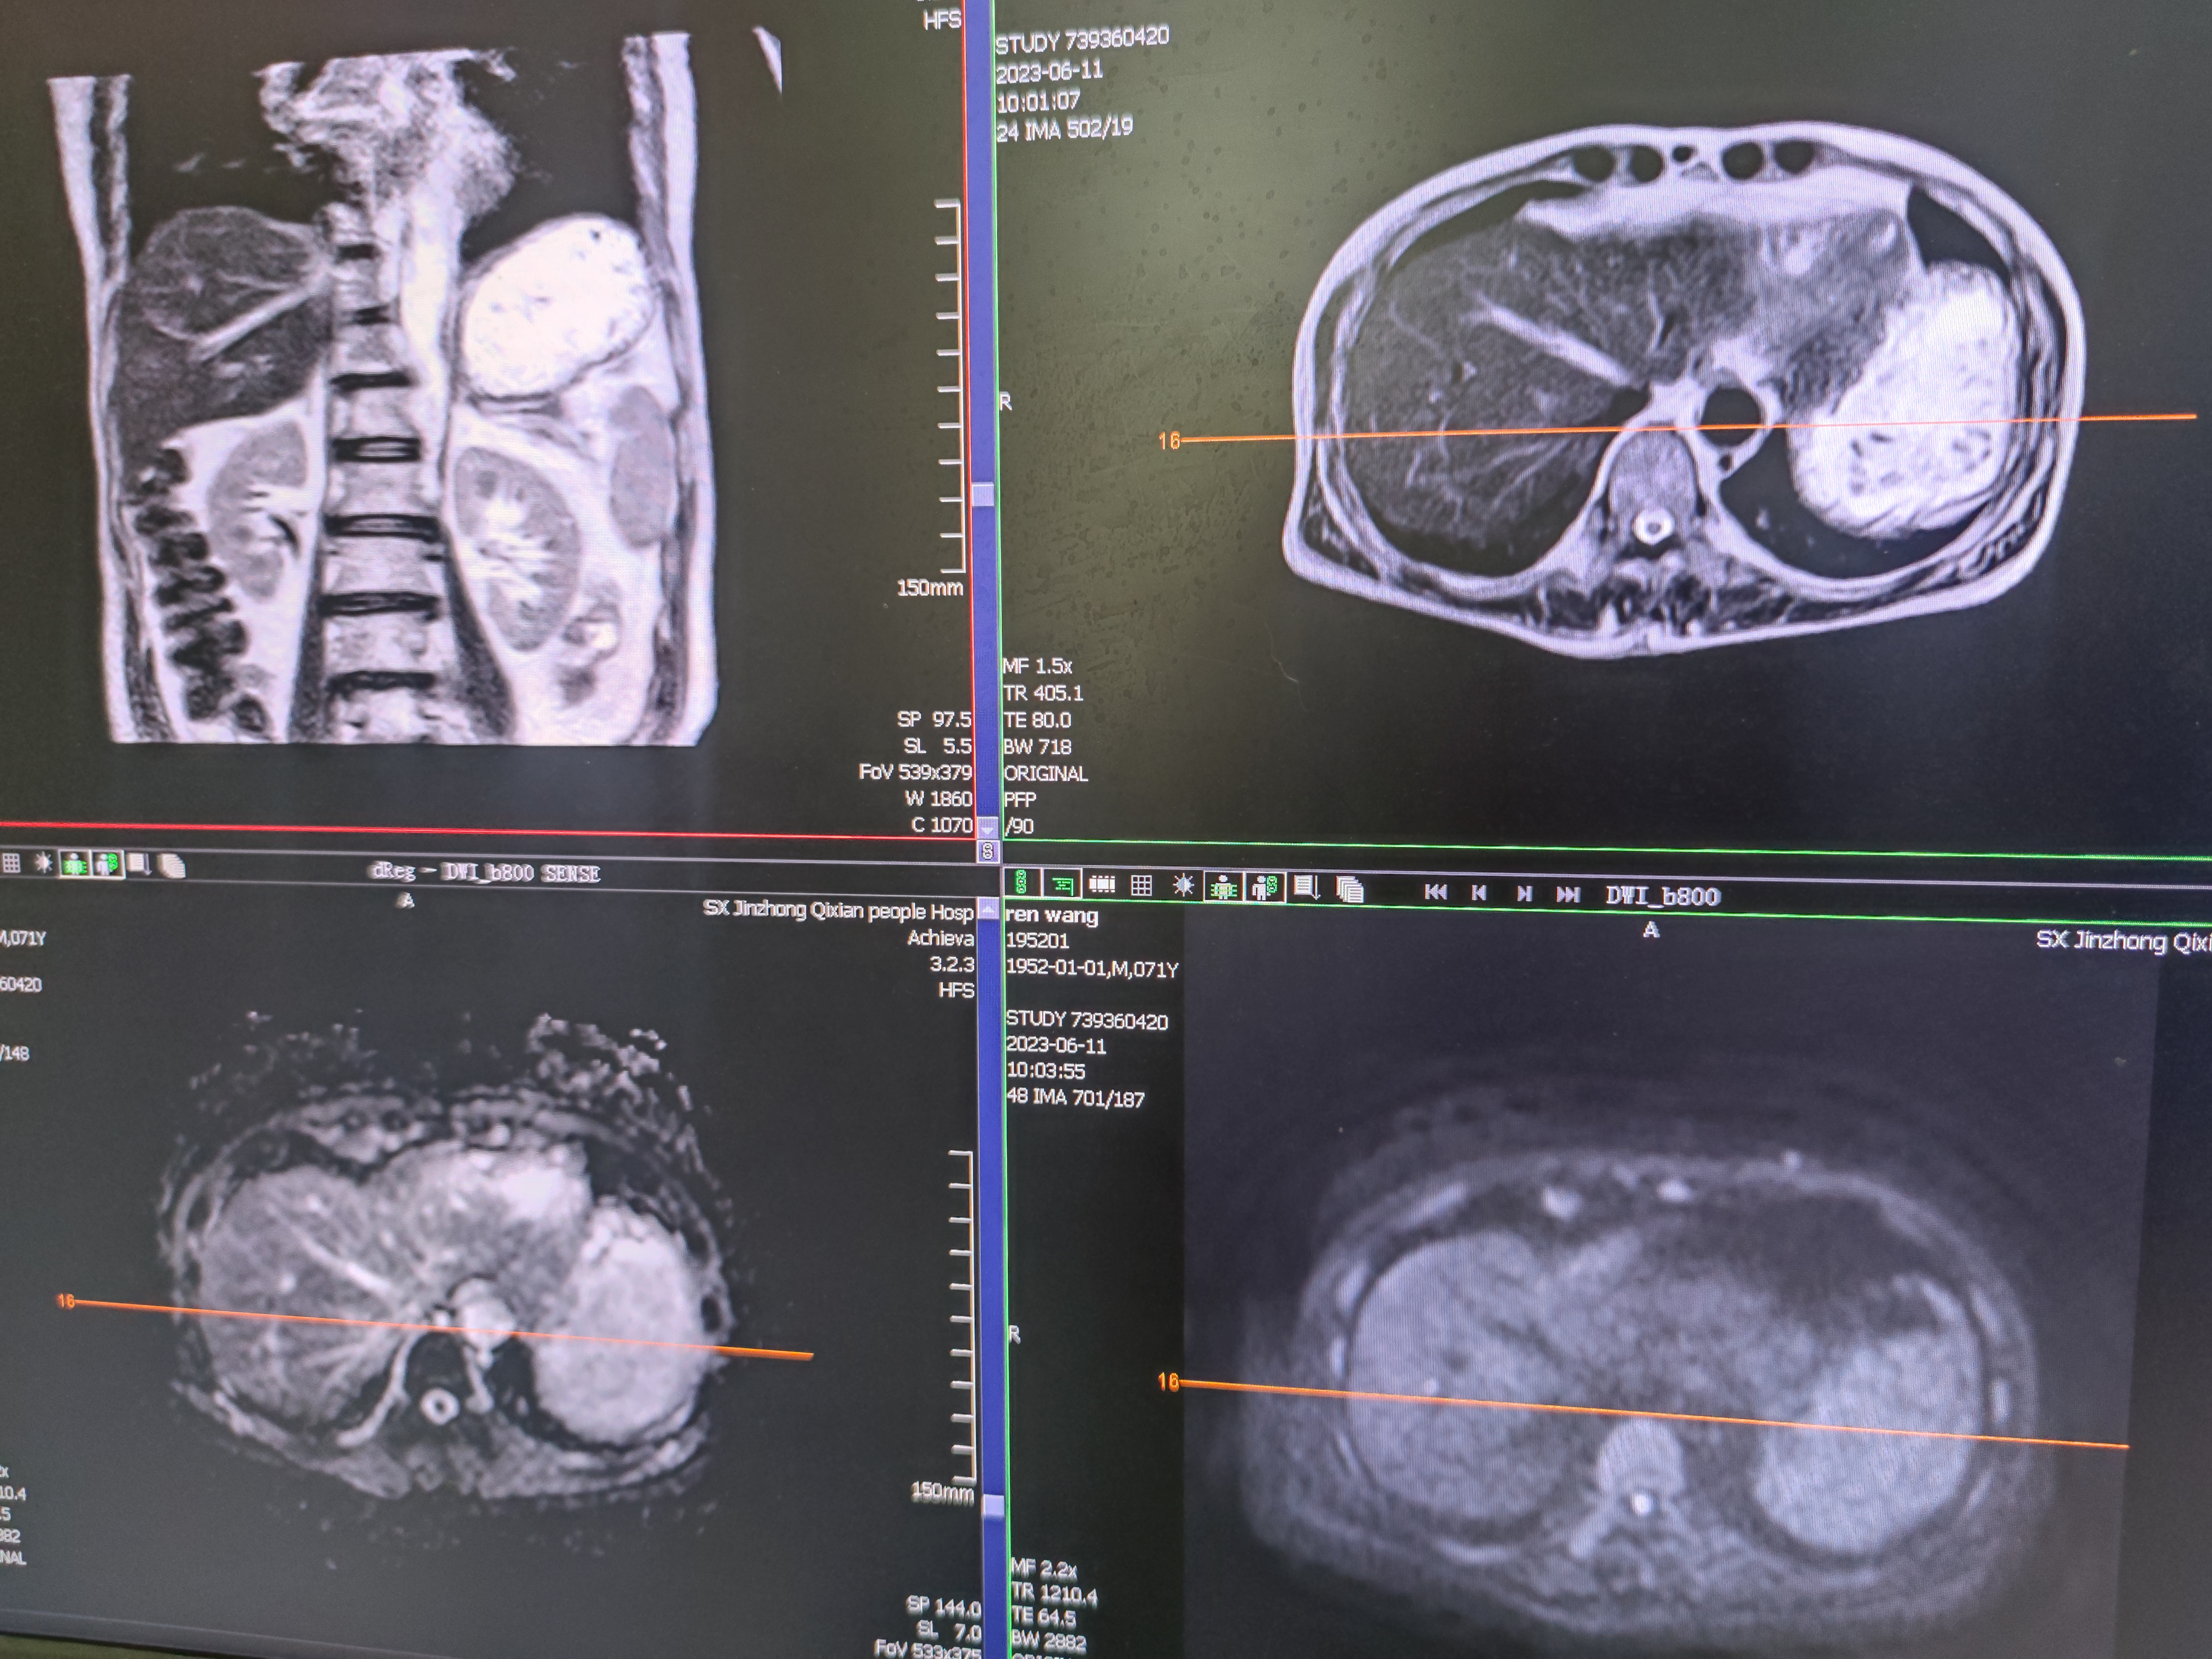

四月份癌胚抗原还是5.6,这个月到8了,持续升高。做了核磁增强,左侧桥小脑角哪有个地方不确定。肝脏核磁平扫弥散有两个点状高信号,转移也排不了,胃肠镜正常,左颈部有个变圆的淋巴结,保险点是不该加个化疗药了?咨询了陈波主任,等结果的吧!图片